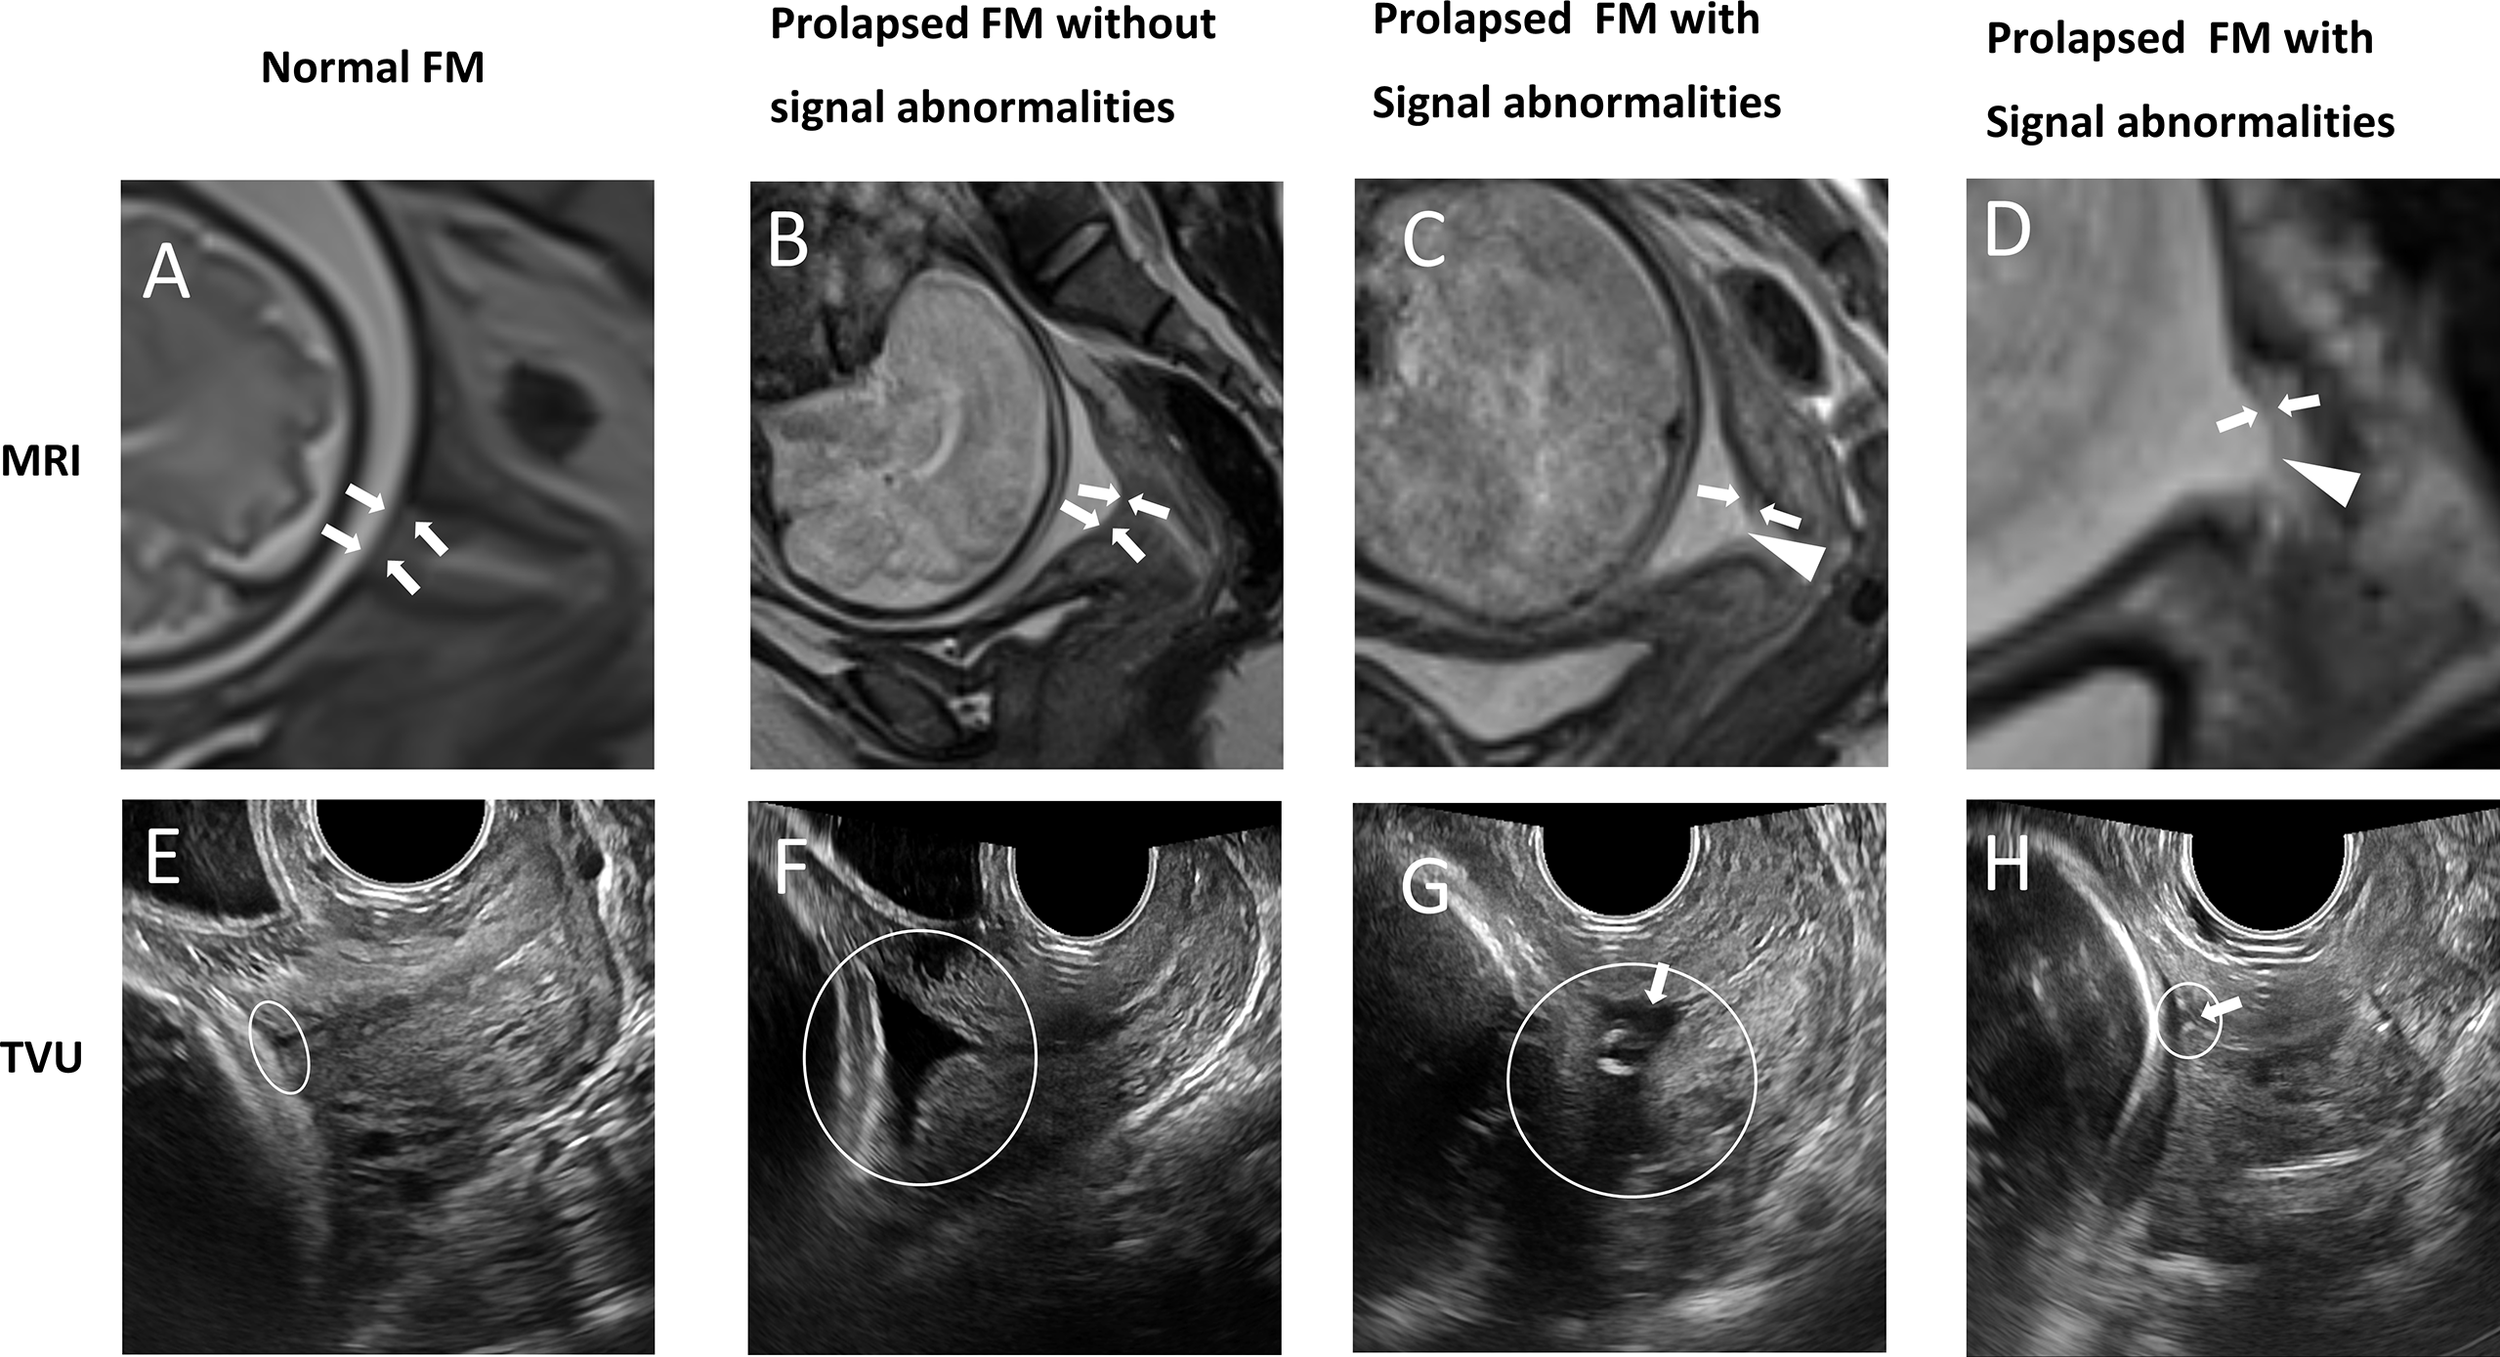

Previous studies have shown that the supra-cervical FM can occasionally be detected by ultrasound in the presence of chorioamniotic membrane separation (6, 24, 25). However, no detailed biological features of supra-cervical FM have been imaged and reported using ultrasound. It is technically challenging to identify FM near the internal os using transvaginal sonography (8). The reasons are two-fold. First, too much pressure from the ultrasound probe forces the anterior and posterior walls of the cervix to adhere together. The compressed internal os reduces the contact area between the FM and the cervical fluid below it. Second, ultrasound waves are reflected at the interface between media with different density (26). If there is no chorioamniotic membrane separation, we cannot observe the interface between the FM and the cervical tissue below it. In comparison, clinical MRI is able to reliably image the entire supra-cervical FM without deforming the cervical internal os. In addition, the supra-cervical FM is surrounded by the superior amniotic fluid, and inferior cervical fluid, both of which have high liquid T2WI signals, and thus can serve as natural contrast agents to highlight the FM (intermediate or low signal). When comparing MR images and transvaginal ultrasound images of the same patient on the same day (Figure 3), it is clear that MRI provides superior tissue contrast and biological characteristic information. In our previous study, we used 3D-CISS sequence to examine the fetal membrane at the cervical internal OS zone (27). Although 3D CISS sequence offers higher spatial resolution, it is not a routine clinical sequence, and not widely used in each of the clinical imaging session.

FIGURE 3

www.frontiersin.org

Figure 3 Patients underwent clinical MRI and transvaginal ultrasound (TVU) examinations on the same day. A vs. E (32wks); B vs. F (32wks); C vs. G (32wks); D vs. H (28wks). Panel (A–D) are MRI T2W images from the sagittal view. White arrows indicate the supra-cervical FM, and white triangles indicate fetal membrane defects. (A) Normal FM. (B) Prolapsed FM without signal abnormalities. (C) Prolapsed FM with signal abnormalities: partial defect of continuous FM signal. (D) Prolapsed FM with signal abnormalities: local thinning and increased signal intensity of continuous FM signal. The FM overlying the cervix is pointed by a white arrowhead. Panel (E–H) are TVU images. White rings indicate cervical internal os. (E) In the patient without prolapsed FM, the entire supra-cervical FM cannot be distinguished clearly due to the compression effect of the ultrasound probe. (F) In the patient with the prolapsed FM, the exact boundary between the supra-cervical FM and the underlying cervical tissue cannot be identified. (G, H) In patients with the prolapsed fetal membrane, the supra-cervical FM is partially visible. However, the signal abnormalities of the supra-cervical FM cannot be detected. White arrows point to the FM.